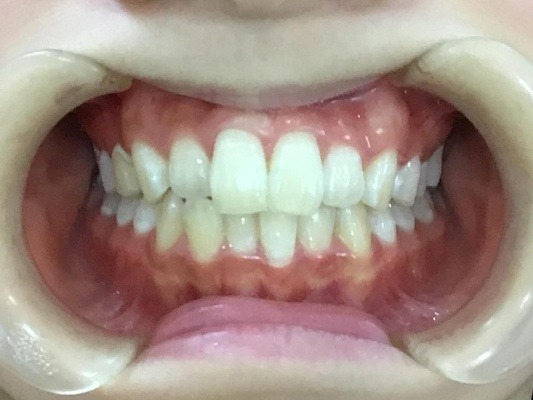

• BEFORE

症例集 インビザライン 正面

矢印

AFTER

正面